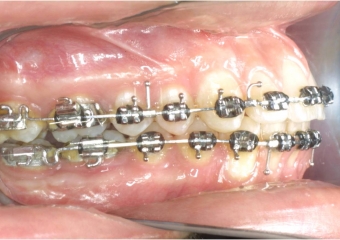

Mordida inicial

Mordida após cirurgia